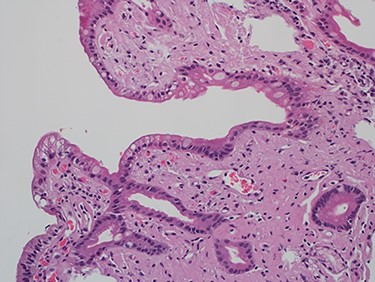

As work up for his abdominal pain and anemia he underwent gastroscopy on 29 October 2020 that revealed congested and nodular gastric mucosa (mass-like) and at lesser extend in the first and second part of duodenum (Figs 1 and 2). Biopsies were taken from the gastric lesion and duodenum. Histopathological findings from gastric mass and duodenum showed marked stromal hyalinosis, which appeared as a cellular pink material on H&E stain (Figs 3 and 5). Congo red stain (amyloid stain) showed apple green birefringence under polarized light on both gastric and duodenal biopsies (Figs 4 and 6).

High power of gastric biopsy showing prominent stromal hyalinosis, (H&E x20).